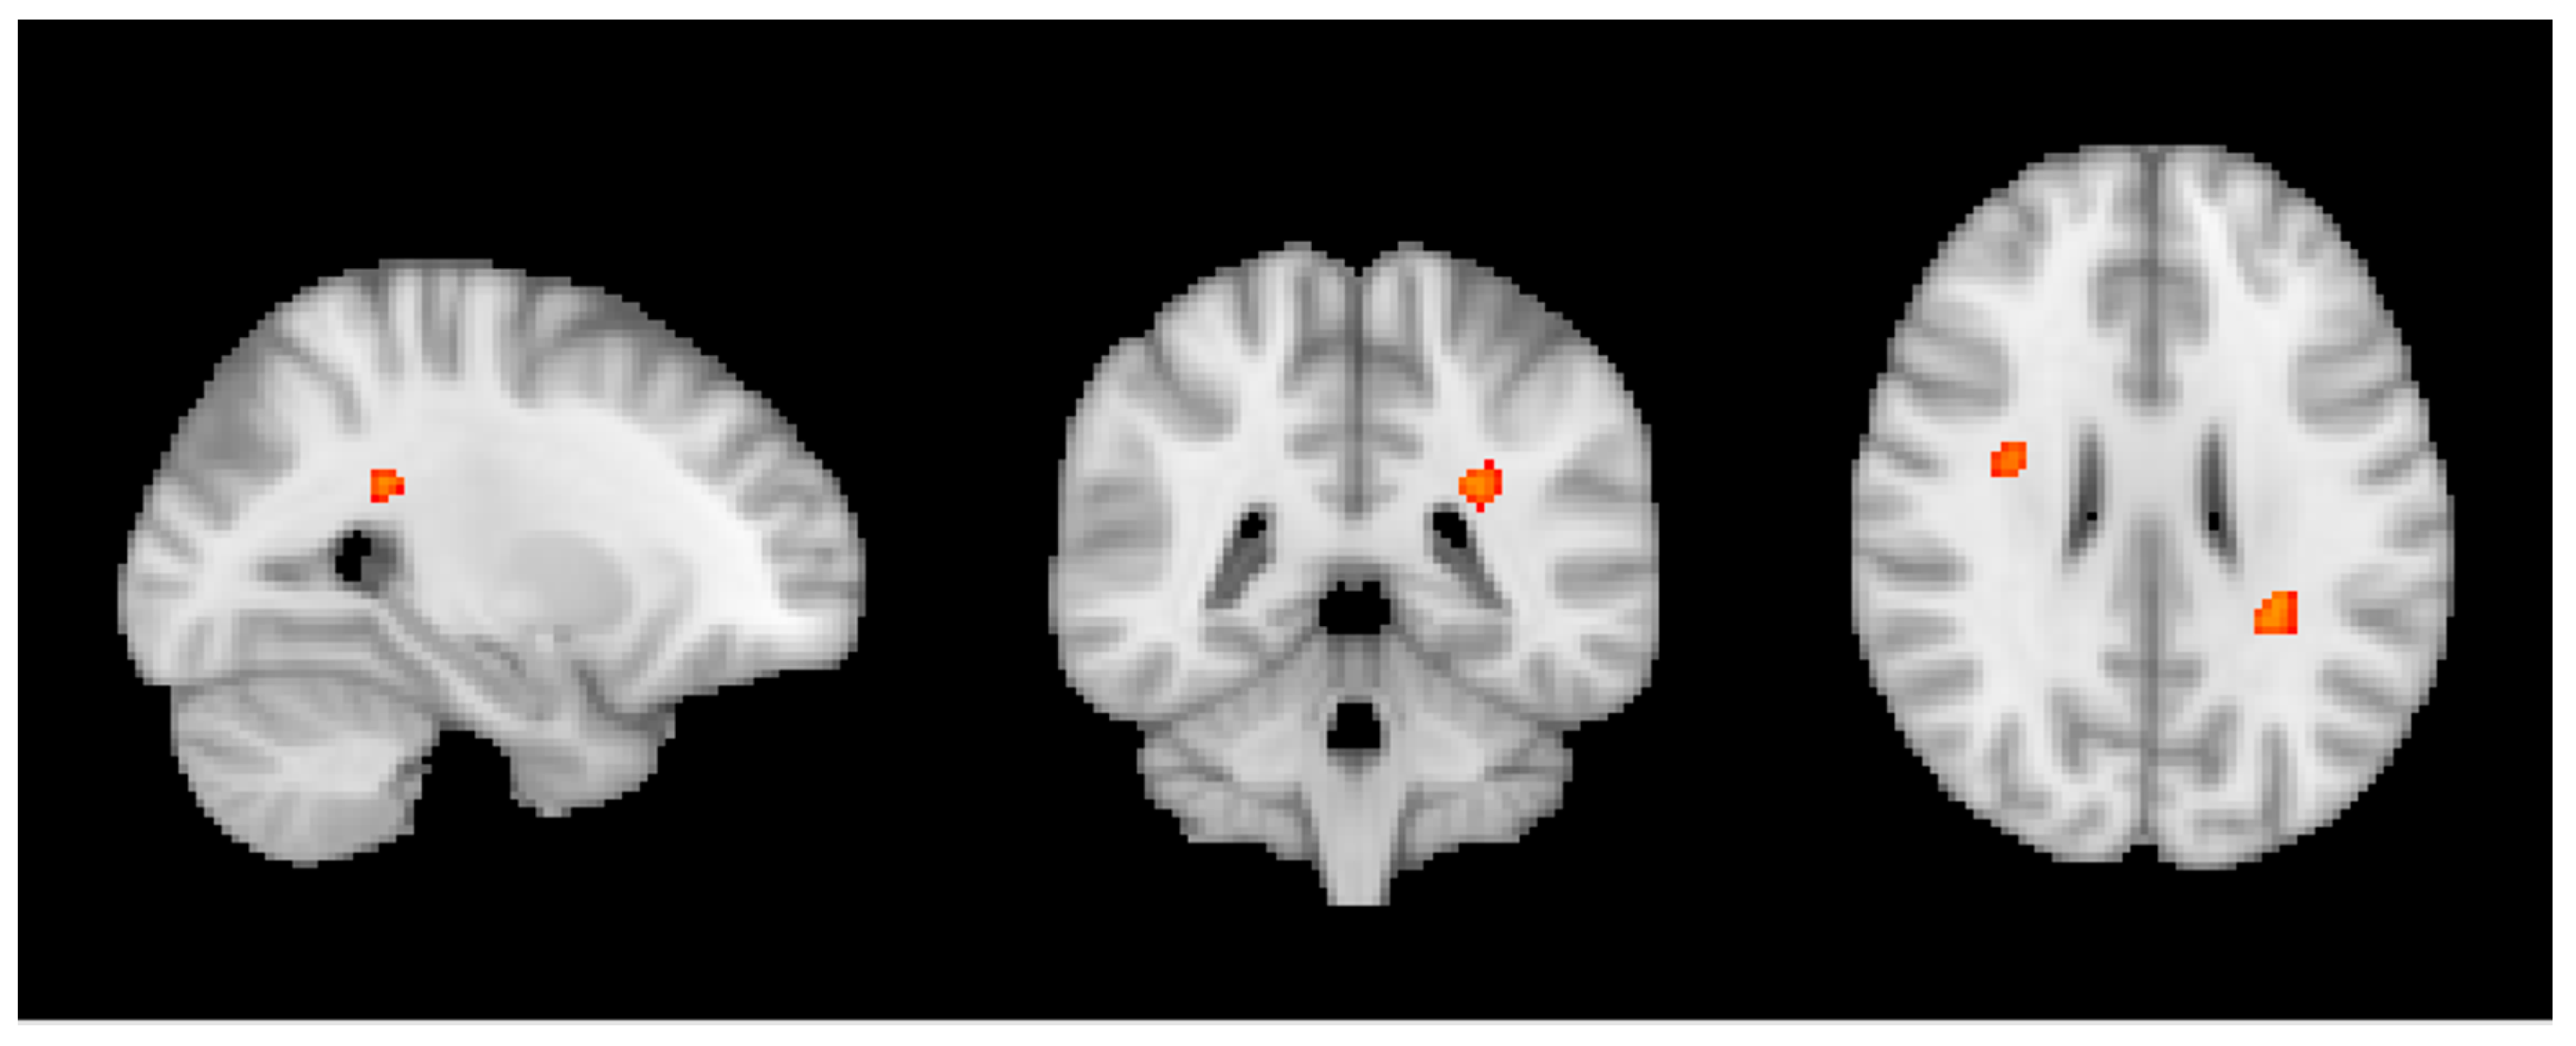

3.2. MRI Analysis across the Entire Group

3.3. Group MRI Analysis